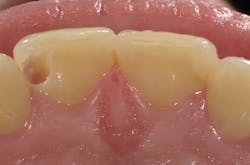

Figure 4

I'll demonstrate this material's versatility with a few cases. First is a large Class III cavity. The patient was extremely apprehensive, so we decided to prepare the cavity using the Lite Touch (AMD Lasers) erbium YAG laser. Very often, as in this case and the next few cases that we will depict, cavity preparation can be performed without anesthetic. In Figure 1, we see the preoperative image of the large Class III cavity on tooth No. 8. Using the Lite Touch laser (figure 2), we were able to excavate the entire cavity in a clean and efficient manner (figure 3). Using a fine diamond, a slight bevel was completed on the enamel at the cavo surface margin. By beveling the enamel, we improve the bond of the adhesive and allow for a seamless blend of the restorative material to the outer tooth structure. In deep restorations such as this, a calcium liner can help minimize sensitivity and act as a buffer between the restoration and pulp. Both Calcimol LC (Voco) and Theracal (Bisco) can be used in this manner. In this case, we decided to use Theracal. Theracal was placed in the deepest area and light-cured for 15 seconds (figure 4). After a 37% phosphoric acid etch of the enamel margin, we applied Futurabond U (Voco) as per the manufacturer's instructions and light-cured for 10 seconds. Admira Fusion shade A2 was placed in three increments and polished. The final restoration exhibits a beautiful luster and a seamless blend from the restoration to the natural tooth (figure 5).